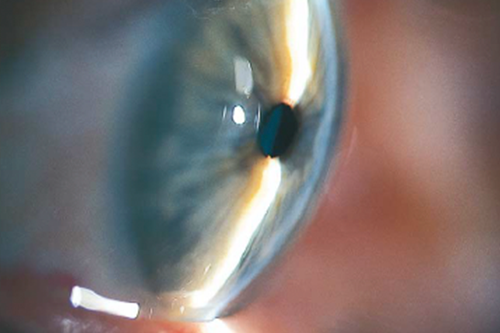

O Glaucoma é a principal causa de cegueira irreversível no mundo. É uma doença crônica e ao mesmo tempo silenciosa, pois o paciente não nota o surgimento da doença até que a mesma tome proporções muito avançadas e com danos graves à visão. No glaucoma, ocorre um dano progressiva ao nervo óptico, normalmente associado ao aumento da pressão intraocular (pressão dentro do olho). O nervo óptico é responsável por captar as informações que enxergamos e transmiti-las ao cérebro. Quando o glaucoma afeta essas fibras nervosas, elas morrem gradualmente, há perda progressiva do campo de visão e pode evoluir à perda total da visão em casos mais avançados.

O principal fator de risco para o glaucoma é o aumento da pressão intraocular. Também há outros fatores de risco como: envelhecimento, histórico familiar, uso prolongado de medicamentos como corticoide, traumas oculares, anatomia ocular com câmara anterior rasa, entre outros.

A suspeita da doença é feita pela medida da pressão ocular e pelo exame clínico do fundo do olho com a observação do nervo óptico. Com essa avaliação podemos identificar pacientes suspeitos que merecem complementação diagnóstica com exames adicionais que irão comprovar ou descartar a doença.

O tratamento depende do tipo de glaucoma (congênito, ângulo aberto, ângulo fechado, secundário a outra condição ocular ou sistêmica, etc) e do estadiamento (gravidade da doença). De modo geral, o tratamento pode ser feito com colírios, laser ou cirurgia, dependendo de cada caso.